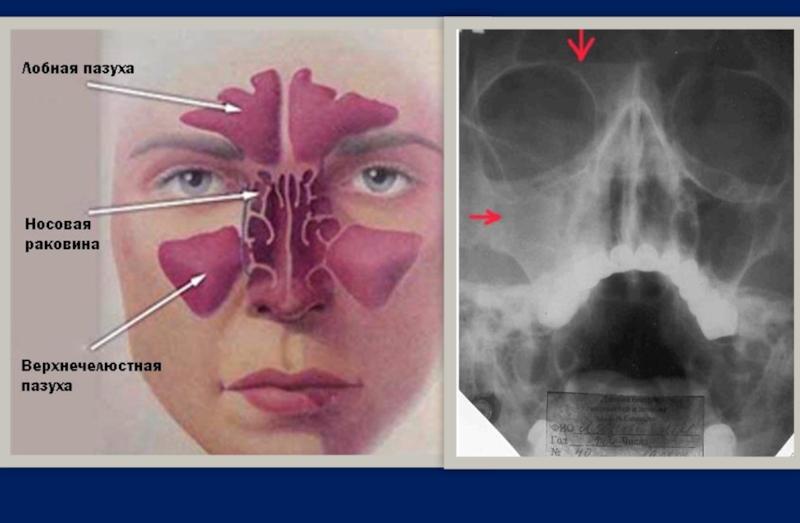

Диагноз ставится на основании данных анамнеза, клинического обследования и результатов дополнительных

методов исследования, в частности рентгенографии или компьютерной томографии придаточных пазух носа.

ДИАГНОСТИКА ГАЙМОРИТА